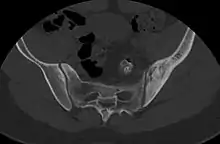

- ↑ Nguyen, Nghi; Khan, Mujahid; Shah, Muhammad (2017). "Primary B-cell lymphoma of the pelvic bone in a young patient: Imaging features of a rare case". Cancer Research Frontiers. 3 (1): 51–55. doi:10.17980/2017.51. ISSN 2328-5249.